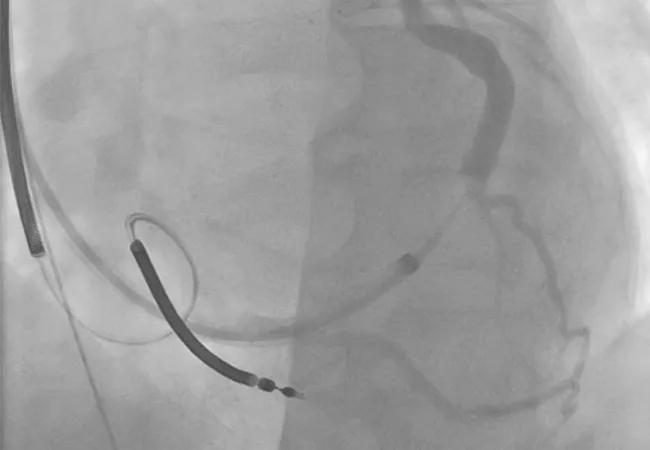

A copy of the patient’s coronary sinus venogram was then obtained (Figure 3) to determine whether another attempt at percutaneous placement would be reasonable. The venogram showed two potential targets:

• The lateral branch was relatively small and tortuous at the proximal portion with a trifurcating system at the ostium that could be accessed but apparently would not accept a lead.

• The posterolateral branch was moderately sized, but a stenosis in its midsection made it unable to accept a lead, although a wire could pass beyond it.

Figure 3. Coronary sinus venogram showing potential targets for percutaneous coronary sinus lead placement at the lateral and posterolateral branches.